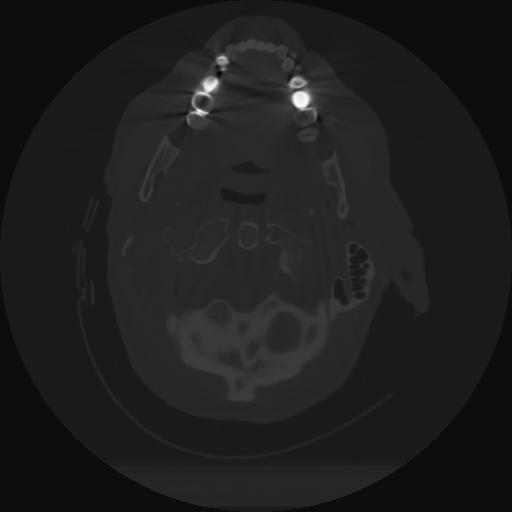

12 P.BLANDAS,,Vol,0.5,P.BLANDAS,,